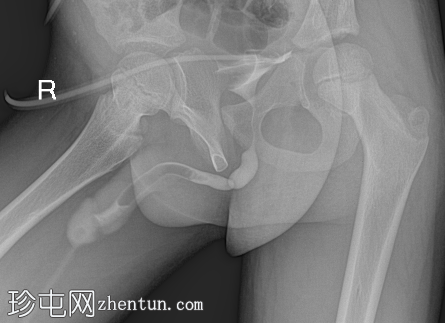

正位

逆行尿道造影显示远端球部尿道存在持续性短段(<1 cm)、环周性明显狭窄,近端轻度扩张。造影剂可自由进入后尿道和膀胱,无外渗。

阴茎尿道充盈缺损为医源性,由注入的气泡引起。